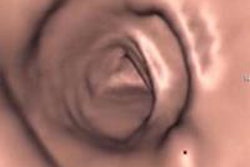

![]() |

| Above, per-patient performance results segregated by bowel prep regimen show significantly improved sensitivity in individuals with 6- to 9-mm lesions who underwent fecal tagging. Below, combined results for detecting adenomas and hyperplastic polyps in all patients again demonstrate significant improvement only in individuals with 6- to 9-mm polyps. |